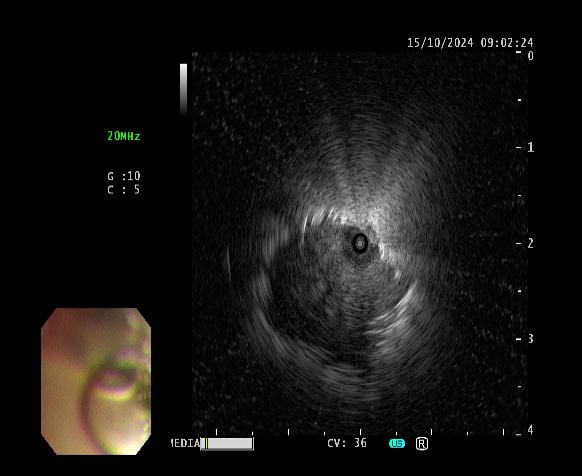

患者女性,因“气短1月”来门诊就诊,为明确诊断进一步治疗,收入呼吸与危重症医学科。入院后完善相关检查,胸部CT示左肺上叶前段高密度灶,与家属充分沟通后,决定为患者行超声支气管镜检查。主任医师吴水淼与主管护师薛冬冬为患者行气管镜检查,镜下示:双肺支气管均未见明显异常,结合CT给予超声探查,于左肺上叶前段亚支探及偏心异常回声区,由于亚支位置较高且管腔较窄,活检钳无法到达,给予冷冻肺活检。此次检查过程顺利,成功获取2块活检标本,活检病理结果提示为粘液腺癌。